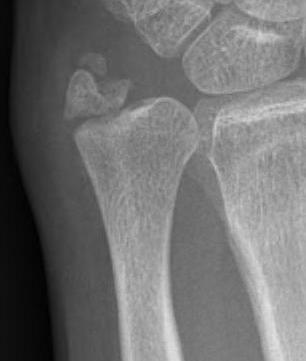

Classification ulna styloid fractures

| Type 1: Tip | Type 2: Base | Type 3: Proximal to styloid |